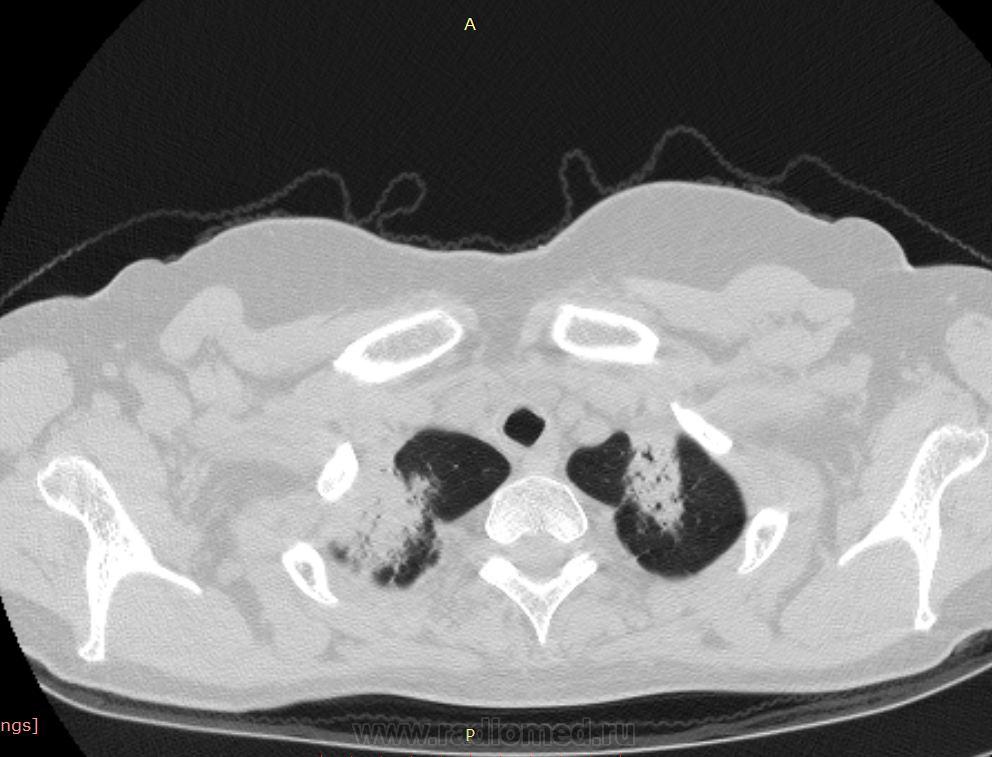

38 лет. 6 лет назад cr носоглотки. Лучевая и химиотерапия. С июля 2012 г. клиника бронхолегочного заболевания.

Флюорография 2010 - норма. В анамнезе хронический гайморит. Бронхоскопия- признаки неспецифического эндобронхита. Исходная флюорография на бумажном носителе с низким качеством изображения. Описаны тени в верхушках легких, воспалительные изменения в средней доле. Лечение макролидами амбулатороно  дало кратковременный эффект.

Узелки хаотичного распределения (туб, микозы, мтс). Участки, напоминающие дерево-в-почках. На верхушках посттуберкулезный фиброз, при этом верхние отделы, насколько можно судить, чистые. Прикорневой фиброз и тракционные бронхоэктазы нижних отделов. Преобладание процесса в нижних долях + фиброзные изменения, +  утолщение??? междолькового интерстиция. Значимой лимфаденопатии не нашла, выпота тоже.

На первое место - неспецифическая интерстициальная пневмония. Спецпневмофиброз верхушек. Насколько возможна реактивация туберкулеза прогнозировать не берусь.

Присоединюсь к ЛГ (со всеми ее оговорками): ДИЗЛ, неспецифическая интерстициальная пневония, участки фиброза, бронхиолита.